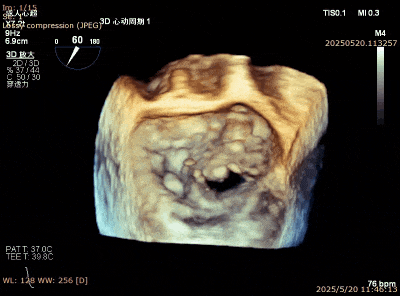

图12. P2大脱垂病例植入第一个夹子后出现夹子歪斜晃动大

图13. 第二个夹子关闭时可将第一个夹子卡入

图14. 反转夹子用输送杆将第一个夹子捋直

图15. 最后结果,双夹比翼双飞